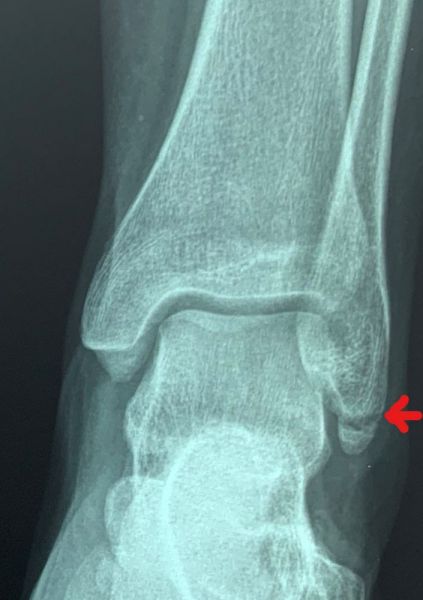

3. Nonunion distal tip of the left lateral malleolus in a 47-year-old female.

Treatment: Open reduction internal fixation with the use of specific grafts

I. Before surgery, anteroposterior view of the ankle II. Four months post-surgery, anteroposterior view of the ankle shows the metal work and the union of fracture